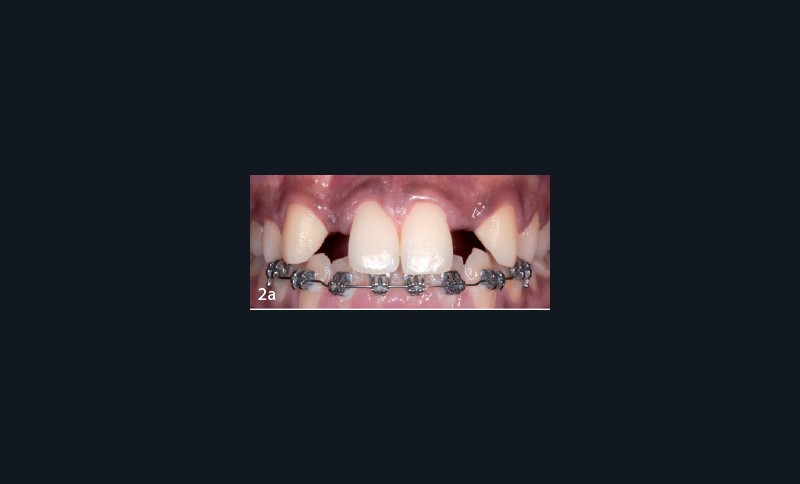

Un traitement multi-bracket est entrepris afin de fermer le diastème inter-incisif et de distaler les canines. Après deux ans et demi, devant un risque avéré de rhizalyse, la décision d’arrêter le traitement s’impose. L’ouverture des espaces est partielle et compatible avec les proportions cliniques souhaitées pour les deux incisives latérales (fig. 2a). Cependant, les orientations radiculaires de même que les largeurs de crêtes dans les deux secteurs édentés (fig. 2b) ne permettent pas d’envisager une reconstruction implanto-portée adéquate.